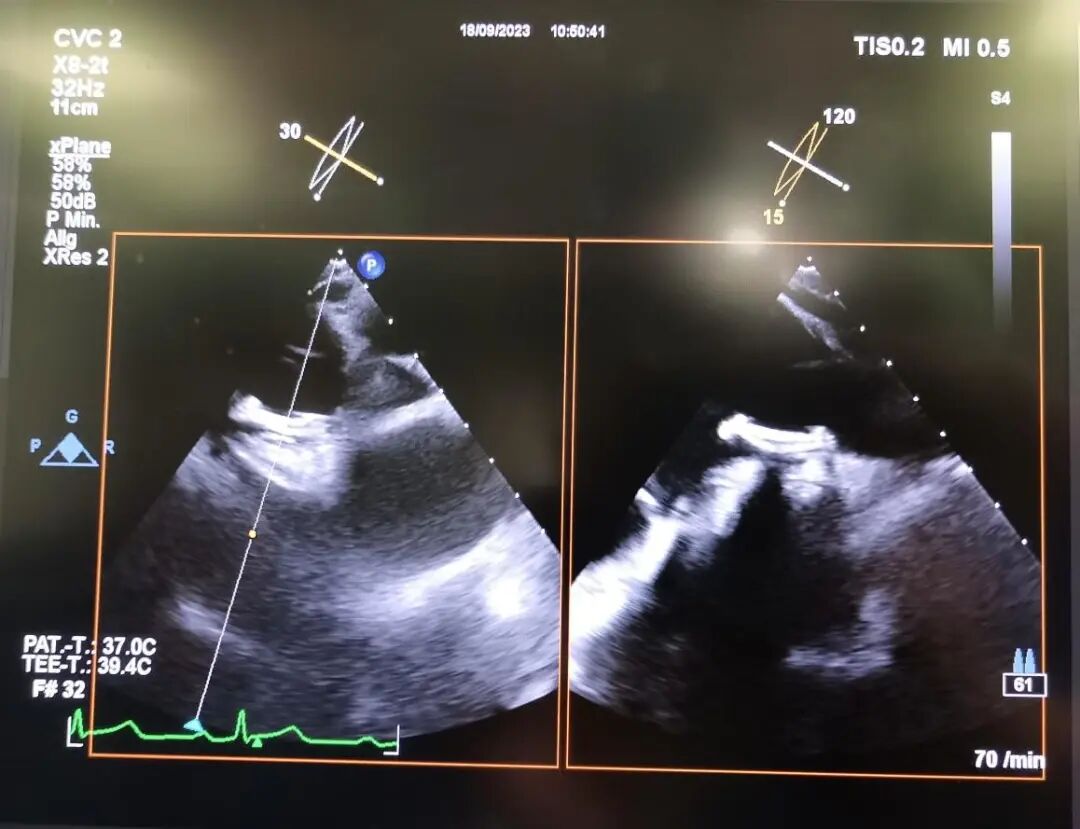

本例卵圆孔未闭患者是严重的金属过敏体质,因此,无法使用金属封堵器,此前曾接受过经皮卵圆孔未闭缝合术治疗,但术后一年多经食道超声心动图显示,仍存在大量右向左分流(Ⅲ级),卵圆孔隧道长度约为6 ~7mm、缝隙最大宽度为1.5~2 mm,卵圆孔缝合处房间隔局部变形,患者反复头痛,并出现脑栓塞,急需进行手术治疗。

术前超声